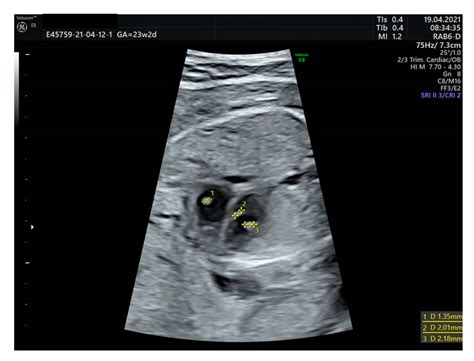

During the first and second trimesters, doctors look for specific anatomical findings. The most well-known screening takes place between 11 and 14 weeks of gestation, known as the Nuchal Translucency (NT) scan. Here are some of the markers that clinicians pay close attention to:

• Nuchal Translucency: This refers to the fluid-filled space at the back of the baby's neck. A thickened NT measurement can be an indicator of potential genetic issues.

• down syndrome ultrasound 12 weeks